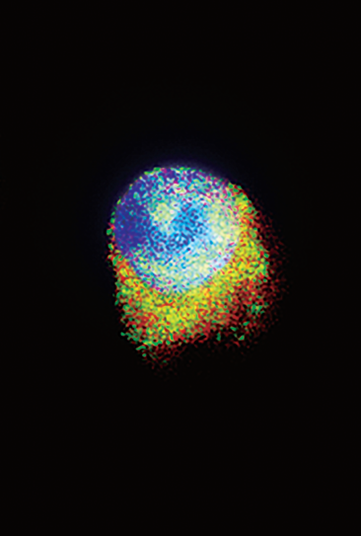

Edited AZI protein (green) translocates from the cytoplasm to the nucleus, enabling its interaction with DDX1 (red) in both the nucleus and cytoplasm. This nuclear binding enables DDX1 to regulate the expression of hematopoietic regulators to sustain normal hematopoietic differentiation. See the article by Wang et al on page 1939.